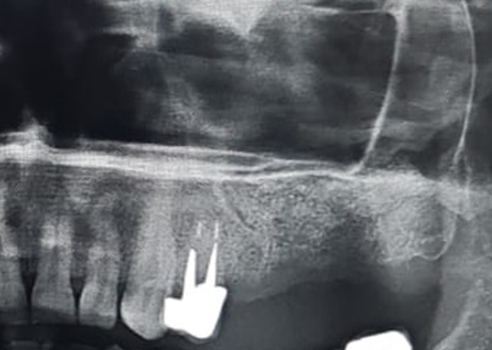

Кстати, рентген только шеи сделали. Голову не стали проверять, хотя он упал прямо на неё и мы об этом говорили, да и по его лицу это было видно.